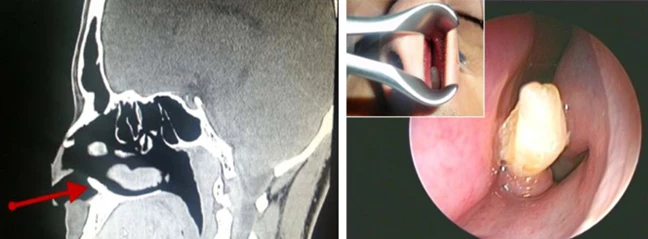

Ο άντρας με το δόντι στη μύτη του

Ένας 22χρονος άντρας κουράστηκε με τις καθημερινές σχεδόν ρινορραγίες του και αποφάσισε να συμβουλευτεί τον γιατρό του. Και βέβαια αυτό που βρήκε ο επιστήμονας μόνο κοινό δεν ήταν: ένα δόντι φύτρωνε κανονικότατα στο αριστερό ρουθούνι του φουκαρά! Είχε μήκος 1 εκατοστό και είχε εμφανιστεί στη βάση της ρινικής κοιλότητας.

Ο χειρουργός αφαίρεσε το παραπανίσιο δόντι χωρίς επιπλοκές και όλα πήγαν όπως έπρεπε. Κι αν το συγκεκριμένο γεγονός είναι σχετικά κοινό (κάπου 0,15%-3,9% των ανθρώπων της οικουμένης πάσχουν από τη γενετική αυτή ανωμαλία), υπάρχουν και φορές που τα γονίδιά μας τα κάνουν εντελώς μαντάρα, και τότε τα πράγματα γίνονται αληθινά τρομακτικά, όπως στην περίπτωση του Doug Pritchard. Ήταν το 1978 όταν το καθόλα υγιές 13χρονο αγόρι άρχισε να νιώθει αφόρητους πόνους στο πόδι, και όπως όλοι μας πια συμπεραίνουμε, ήταν γιατί φύτρωνε ένα δόντι εκεί μέσα! Ε ναι, σωστή ταινία τρόμου…